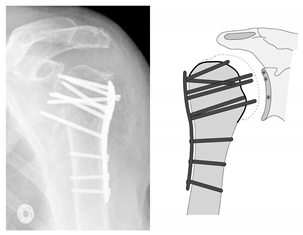

| Complication Type | Exemplary Images by X-rays or Pattern Images | Definition |

|---|---|---|

| 4 | ![]() | Complication Type 4a is based on the presence of AVN of the humeral head without concomitant destruction of the glenoid articular surface due to an associated screw cutout through the humeral head cortex. |

| 4b | ![]() | Complication Type 4b is also based on the presence of an AVN of the humeral head combined with a destruction of the glenoid articular surface due to the associated screw cutout through the humeral head cortex. |